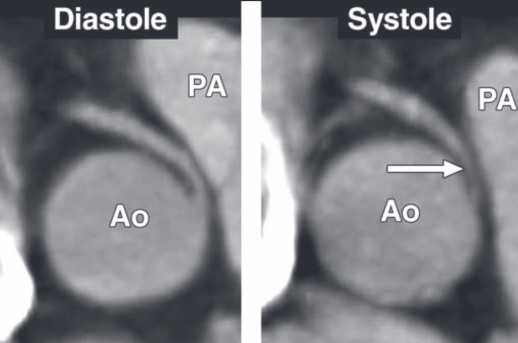

Naissance de la CD du sinus coronaire gauche avec trajet malin et compression en systole, risque de mort subite

“Slit-lile” ostium

Anomalie avec naissance du sinus gauche, trajet interarteriel et “slit-like” ostium